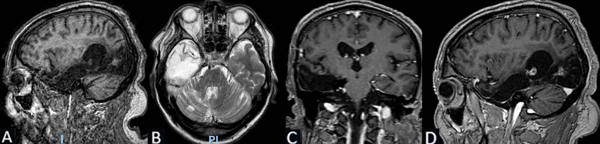

Se solicita RM cerebral con contraste, de cortes finos, donde se evidencia en secuencia T1 imagen de aspecto globuloso en la región hipocampo amigdalina paramediana derecha, ligeramente hipointensa de 2.7 x 2.5 x 1.3 cm. En T2 se comporta como hiperintensa, sin efecto de masa, sin edema perilesional. No presenta cambios posteriores a la inyección del medio de contraste (Figura 2).

Figura 2. Caso 2: RM de cerebro. A) Secuencia T1. Corte sagital. B) Secuencia T2. Corte axial. C) Secuencia T2 “TIRM Dark Fluid”. Corte coronal. D) Secuencia T1 con contraste. Corte axial.